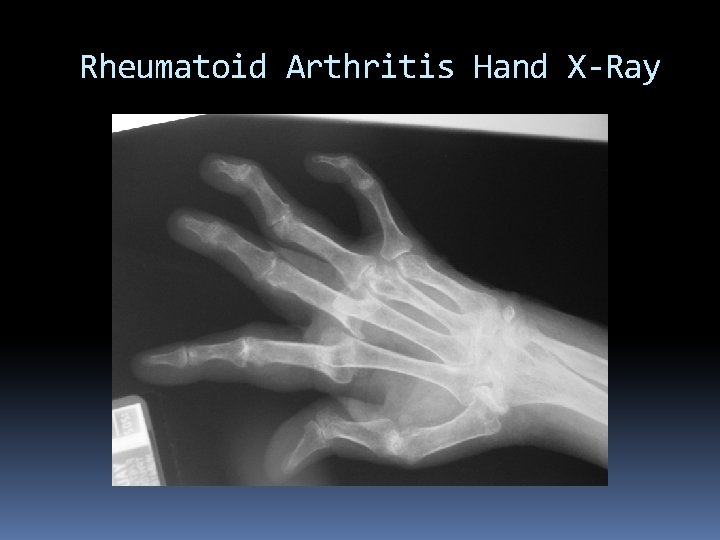

X-Ray - The most common form of medical imaging. An X-ray is high-energy radiation that can easily penetrate materials such as skin and tissues but cannot easily penetrate metals and bone. A radiograph is produced when X-rays pass through the body to produce an image. X-rays are absorbed by dense structures such as bone, the bones appear whiter than other structures

X-Ray Radiographs can be used to check for cancer and to diagnose problems in the cardiovascular and respiratory systems. Using X-rays to image the body is quick, virtually painless, and non-invasive.

X-Ray X-ray is high-energy radiation, and it can cause changes and mutations to DNA. When a radiograph is taken, parts of your body may be covered with a protective lead apron because X-rays cannot penetrate certain thicknesses of lead.

Rheumatoid Arthritis Hand X-Ray